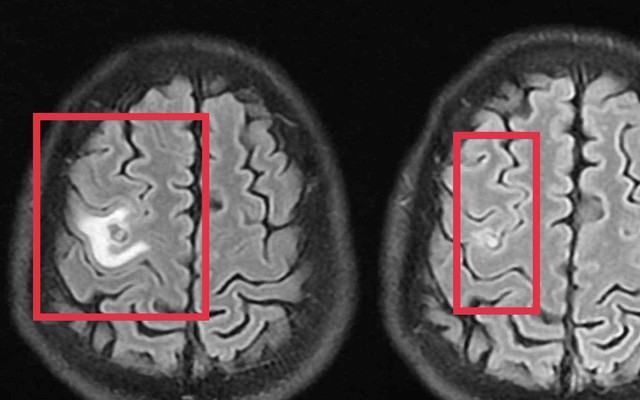

Sau khi các bác sĩ thăm khám và chụp cộng hưởng từ sọ não phát hiện một nang nhỏ ở thùy trán trái, kích thước khoảng 11 x 7 mm, kèm phù não nhẹ. Hình ảnh gợi ý tổn thương do ký sinh trùng hơn là u não nguyên phát. Xét nghiệm huyết thanh học kháng thể kháng sán dây chó dương tính, xác định chẩn đoán tổn thương não do ký sinh trùng.

Khi tái khám gần một tháng sau, chụp cộng hưởng từ cho thấy nang não thu nhỏ rõ, phù não giảm, không còn dấu hiệu tiến triển, đáp ứng điều trị tốt.